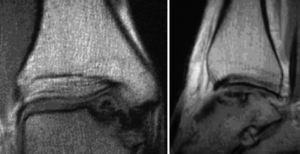

Figuras 14a y b

Radiografías del tobillo en dos planos, a las 6 semanas de la intervención. Las cabezas de los implantes están recubiertas de fábrica con un marcador radioopaco, se identifican en la imagen como puntos. El bloque de hueso ha consolidado sin escalones y apenas se diferencia del hueso circundante. El cilindro está en una posición perfecta pero no se ha integrado completamente.